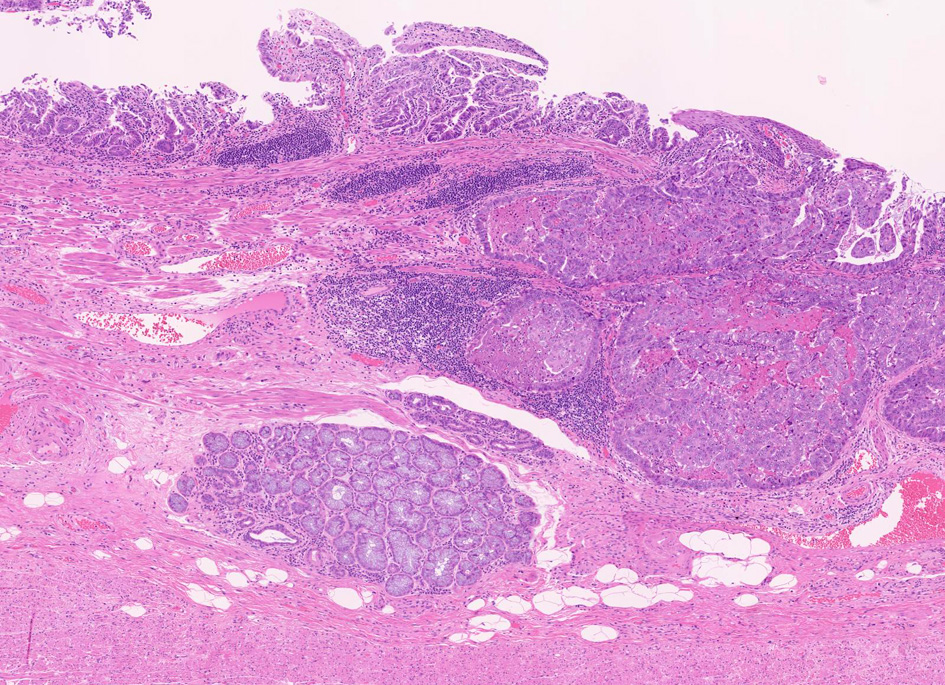

生検・手術での診断

1. 固有食道腺と導管が円柱上皮部位に存在する確定診断

2. 円柱上皮下の粘膜筋板二重化:かなり確実な所見,8割はあたり

固有食道腺(Esophageal Glands Proper:EGP)とは何か

EGPは常に扁平上皮から誘導されてできる腺で, その存在は必ず一度は粘膜内に扁平上皮があったという印であり食道固有の構造である。

扁平上皮島連続切片の観察では,すべての扁平上皮島は固有食道腺と導管を介して結合している

固有食道腺の開口部は必ず扁平上皮で囲まれており, 食道腺の上皮が進展しBarrett上皮ができるとする由来説は誤りである。